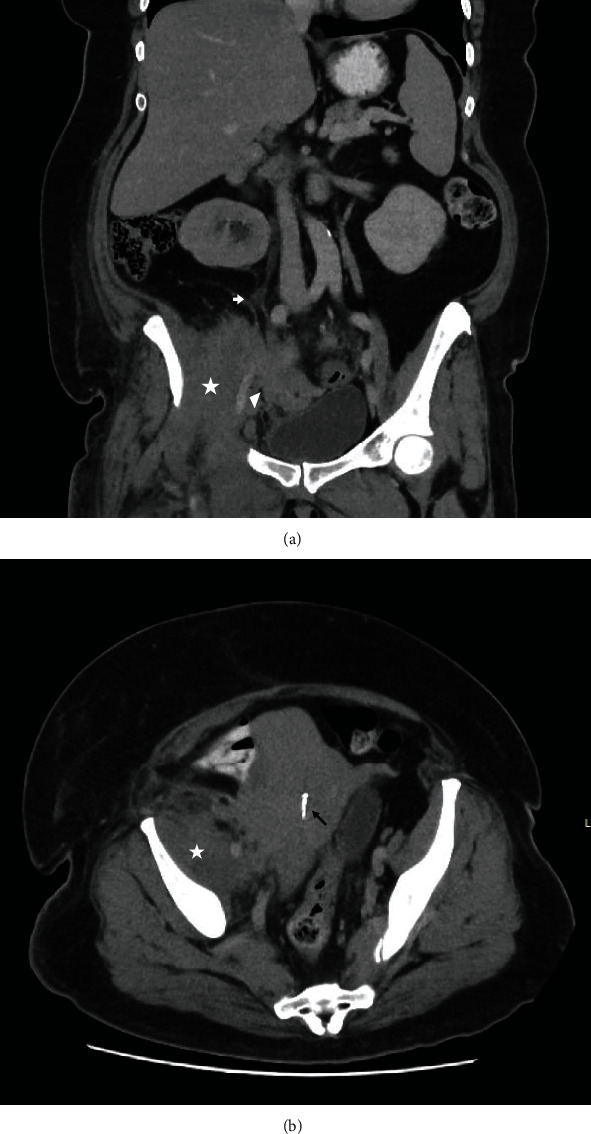

髂腰肌痰肿/脓肿并不常见,患者通常表现为非特异性症状。诊断通常比较迟缓,几乎总是需要先进的成像技术,如计算机断层扫描或磁共振成像。我们报告了一例 51 岁女性的病例,她出现右下肢肿胀并伴有皮疹,造影显示髂腰肌脓肿继发于宫内避孕器感染。这一罕见病例强调了髂腰肌脓肿的非特异性表现,以及在妇女出现髂腰肌痰液和脓肿时考虑宫内避孕器等非正常感染源的必要性。

Iliopsoas phlegmon/abscess is uncommon, and individuals often present with nonspecific symptoms. Diagnosis is often delayed and almost always requires advanced imaging techniques such as computed tomography or magnetic resonance imaging. We report a case of a 51-year-old woman who presented with right lower limb swelling and associated rash with imaging demonstrating iliopsoas abscess secondary to an infected intrauterine contraceptive device. This rare case highlights the nonspecific presentation of iliopsoas abscess and the need to consider unusual sources of infection such as an intrauterine contraceptive device in women presenting with iliopsoas phlegmon and abscess.